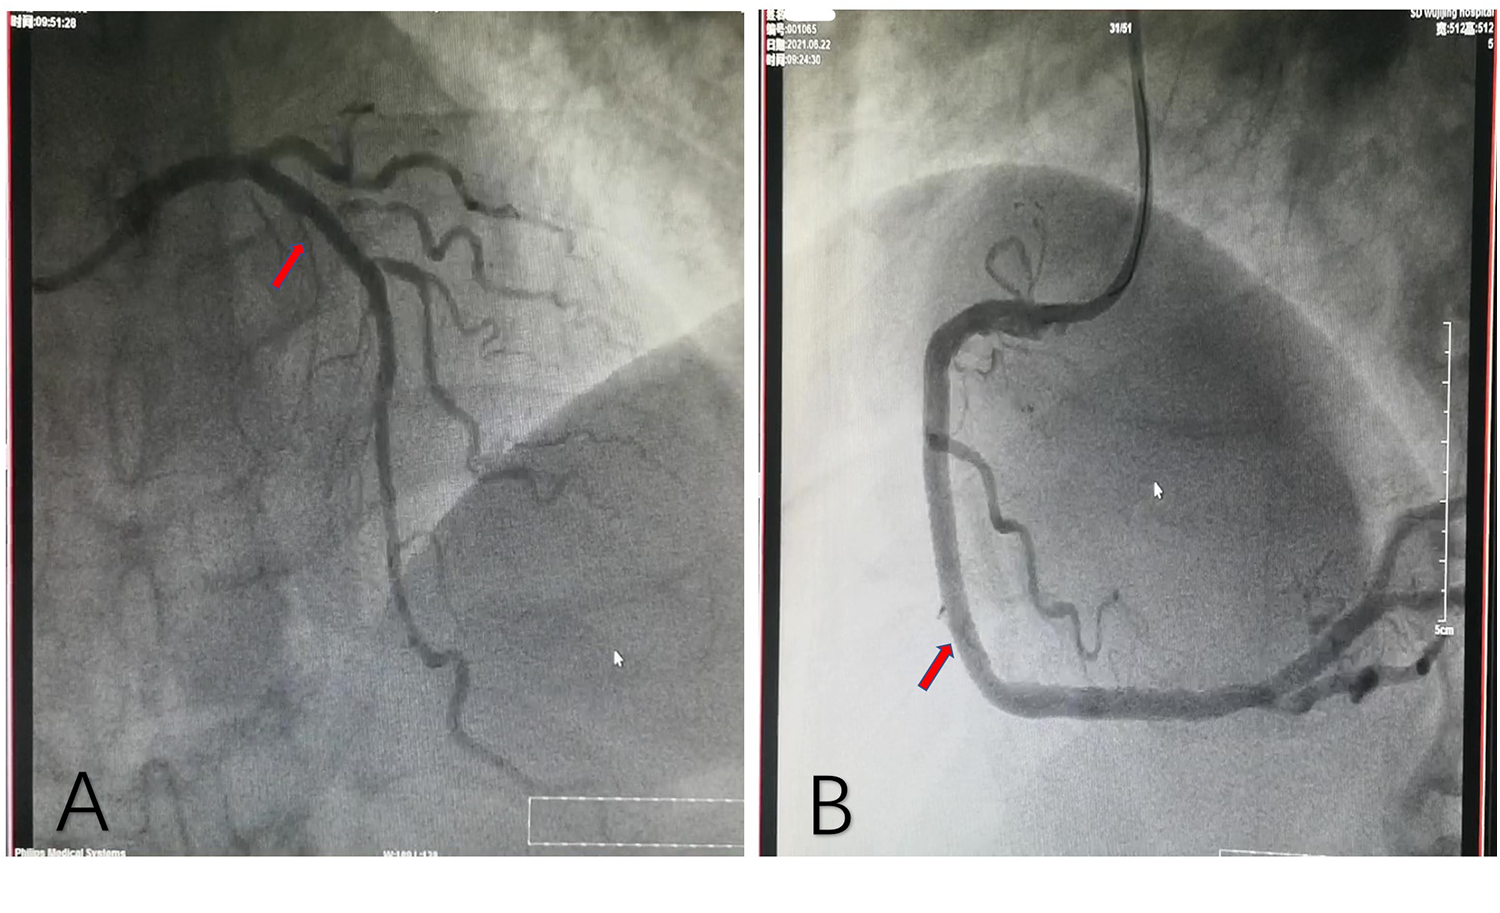

The patient, a 77-year-old man, was admitted due to “sudden unstable chest pain.” Resting for 15–20 min could alleviate the patient's chest tightness in the 2 months before admission. Half an hour before admission, the patient experienced chest tightness again during physical activity and was admitted to the emergency department with chest tightness lasting for 40 min. This patient had a history of hypertension for more than 10 years and oral administration of 80 mg valsartan and 5 mg amlodipine tablets daily has controlled his blood pressure (BP) to normal. The patient has a smoking history of 50 years, accompanied by 10 cigarettes per day, and his mother has a history of cerebral hemorrhage. Upon admission, physical examination showed a BP of 154/75 mmHg and heart rate of 68 beats/min; no significant abnormalities were observed during cardiopulmonary auscultation. There was no edema in both lower limbs. An ECG examination immediately upon admission showed sinus rhythm and ST-T changes, and the patient was preliminarily diagnosed with acute coronary syndrome (ACS). The patient refused a coronary intervention examination and received dual antiplatelet, statin, and nitrate therapy. The blood TNI titer was monitored and increased to 0.727 ng/ml (0–0.023 ng/ml) 12 h after admission. Fasting blood glucose was 4.95 mmol/L. The titer of low-density lipoprotein cholesterol was 2.54 mmol/L. The blood indicators of liver and kidney function were found to be normal. Cardiac Doppler ultrasound indicated normal cardiac structure and function. Three days after admission, the patient agreed to undergo coronary intervention treatment. Coronary angiography (CAG) showed 50% stenosis in the distal left main trunk (LM), 95% stenosis alongside a blurred lesion edge in the proximal LAD (Figure 1A), and approximately 75% stenosis in the middle segment of the right coronary artery (RCA) (Figure 1B). LAD was identified as the criminal vessel and one stent was inserted (Figure 2A). Later, one stent was inserted into the middle RCA (Figure 2B). After discharge, the patient underwent standardized secondary prevention and treatment for CAD and no further chest tightness occurred.

Figure 2

Coronary angiography after stent implantation. (A) One stent implanted in the proximal LAD. (B) Another stent implanted in the middle RCA. LAD, left anterior descending artery; RCA, right coronary artery.